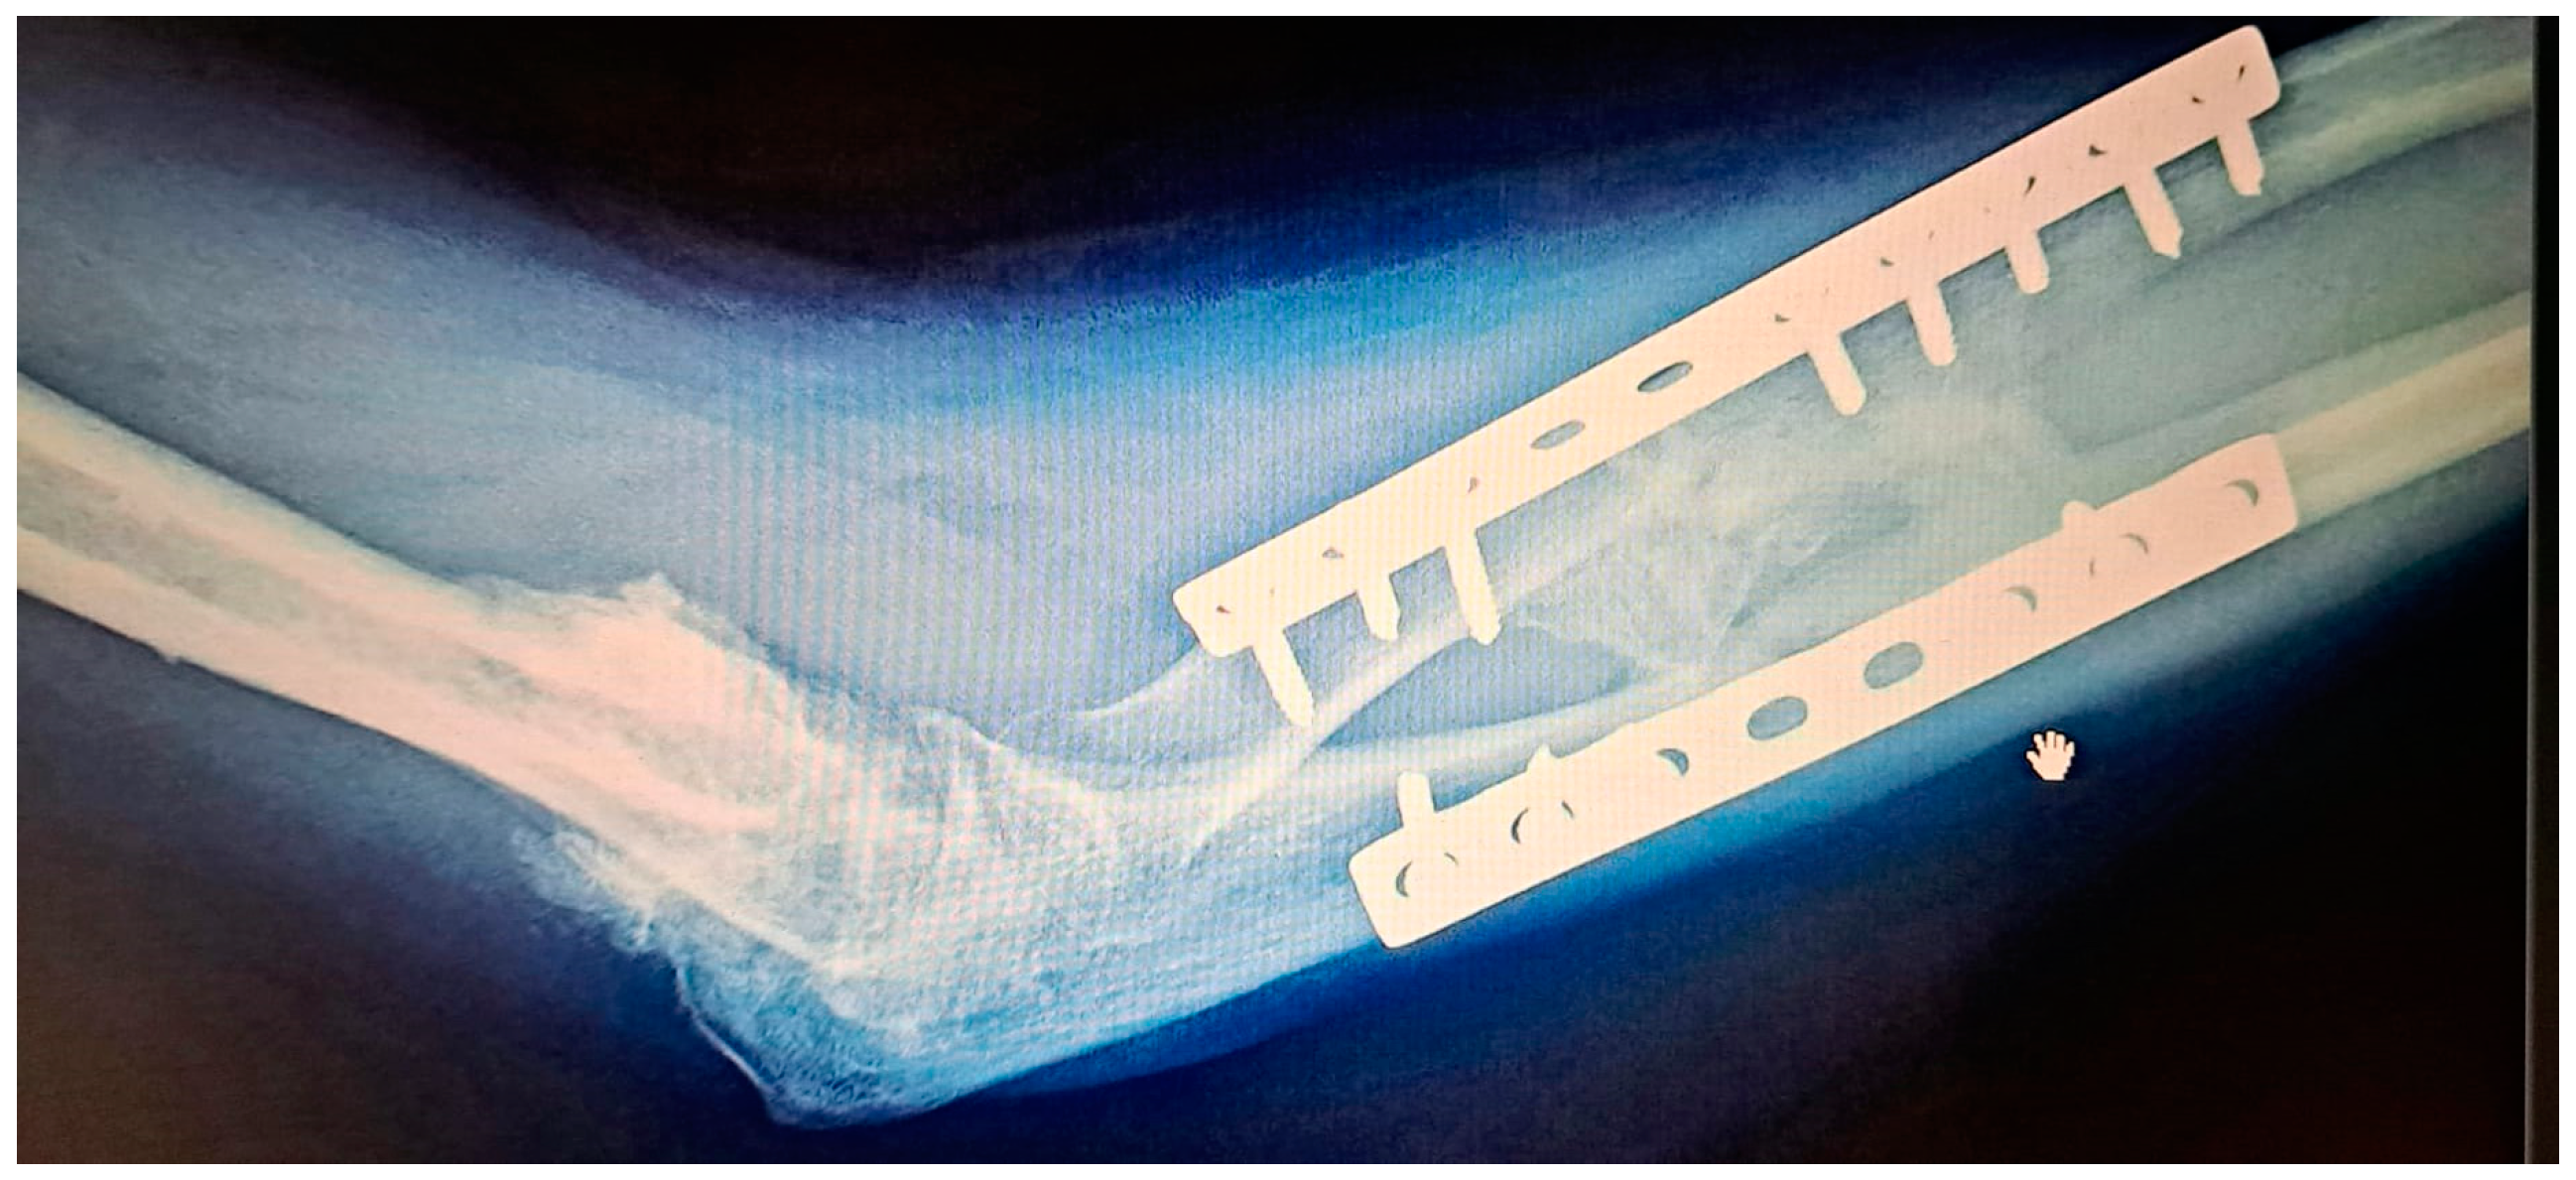

While there is general agreement regarding early intensive rehabilitation, there is no consensus about which is the best protocol. (Figure 4 and Figure 5). The protocols consist of passive and active physiotherapy sessions, splitting in maximum pronation and supination between them [31,44]. The rehabilitation time can sometimes be long and frustrating for the patient. Usually, after the surgery, mobility should be considerably improved. To maintain this result, early mobilization of the forearm (the next day after surgery in prone and supine position) is mandatory. To prevent stiffness, the patient can be placed with the forearm in extreme supination for a few hours, or in pronation position with the help of a cast or splint. The splints are alternately replaced. The patient should know that some degree of motion can be lost during the process due to the retraction of the soft tissue or insufficient mobilization, but if there is no recurrence, the results are very good.

Figure 4. (a) A 49-year-old patient with fractures of both forearm bones and severe brain trauma who developed postoperative radio-ulnar synostosis. (b)The patient was operated on for synostosis a year after the first surgery. The patient received Indomethacin postoperatively for 6 weeks and began postoperative rehabilitation the next day.